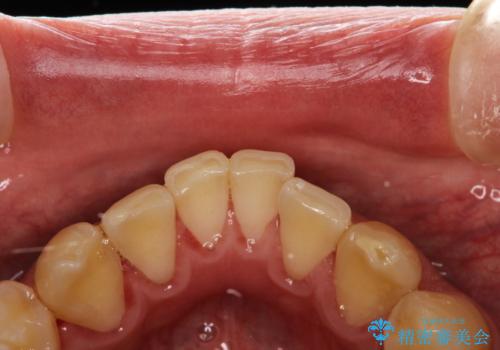

PMTCで歯の着色落とし

- 歯の着色・汚れが気になるとのことでクリーニンング希望とのことでした。PMTC30分コースを行いました。

プラーク(細菌の塊)や歯石がたまると歯の表面はザラつきいてきます。そのザラつきは歯周病や虫歯菌の棲家となります。そのまま放置すると、歯肉が腫れてきたり、歯肉から出血したり、口臭が強くでたりします。とくに歯肉の境目は、歯磨きで汚れを除去することが難しく、プラーク(細菌の塊)や歯石が溜まりやすい場所です。

歯並が、がたついている場合はなおさら汚れが溜まりやすいです。矯正治療前や定期的にPMTCをすることで、歯肉トラブルを防ぐことにつながります。